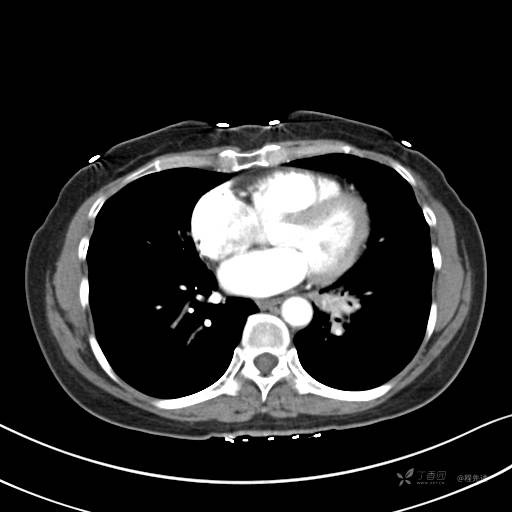

纵隔窗

病灶平扫CT值约31HU